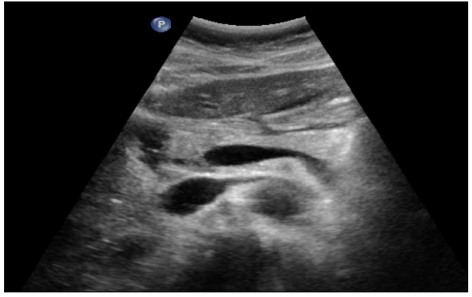

Initiation à l'échographie abdominale

Cliniciens : Formation Continue

DANSE E. - UCL

Digestif US